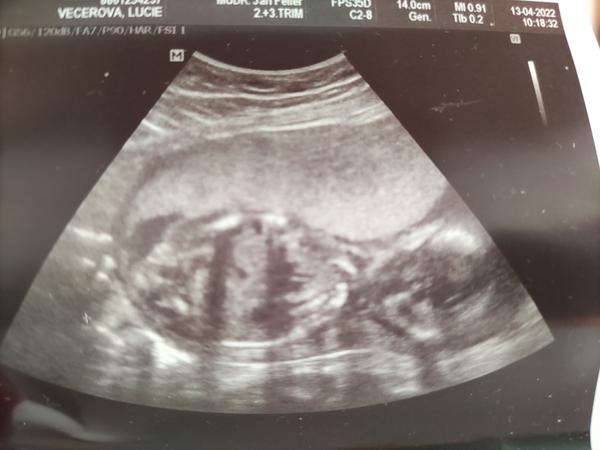

chtěla bych se s vámi poradit, co si myslíte, že čekáme 🙂, určitě máte některé zkušenější oko než my a jelikož jsme od doktorů slyšely obě varianty, ráda se poradím i s vámi, určitě jste takových obrázků už viděly spoustu 🙂. Přikládám foto z UTZ ve 20.týdnu. Moc děkuji!

Holky moc děkuji za reakce 🙂. Mně se to také spíše zdá jako holčička, pan doktor nám ale právě během této kontroly řekl, že tam vidí spíše kluka, což mě dost překvapilo 😃. Je mi jasné, že jistotu budeme mít až po porodu, ale spíš jsme prostě zvědaví 🙂.